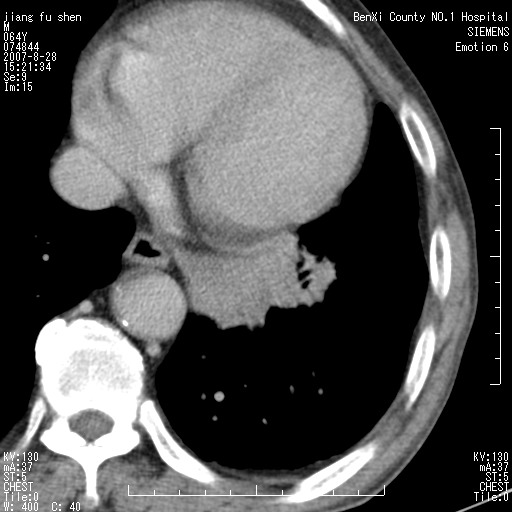

男、64、咳嗽、发烧一周、左肺呼吸音稍弱。既往肺结核,右手结核。

本次扫描患者未带原片,左肺下叶发现病灶。左肺上叶空洞,5组淋巴结肿大,1cm左右。

平扫20-33hu

增强31-33hu

1分半44-52

2分55-67

考虑左肺中央型肺癌并阻塞性肺炎

考虑左肺中央型肺癌并阻塞性肺炎,建议纤支镜检查